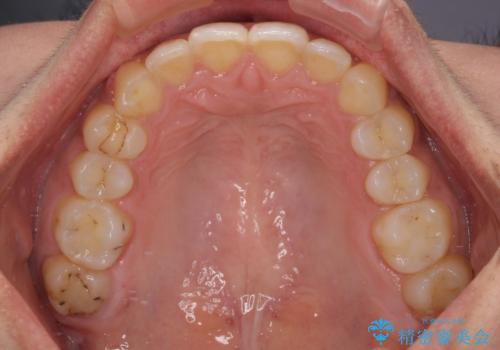

深い咬み合わせと前歯のデコボコ インビザラインによる矯正治療

治療途中では、左右ともに奥歯が咬みにくい状態が続き、問題なく噛めるようになるまでに長期間を要しました。

一方で、デコボコや下顎の前歯が隠れてしまうほどの深い咬み合わせはしっかりと改善されました。